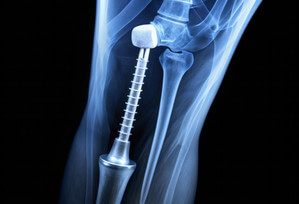

骨螺钉用于在手术中单独或与钢板等其他辅助工具一起稳定骨骼,精确的设计对于安全有效的外科手术至关重要,因为可以确保在置入过程中将损伤降到最低,并降低患者的风险。

车削零件(如骨螺钉)的生产面临诸多挑战,需要专业知识和精确度,以确保最高标准的手术精度和患者安全。

克服这些挑战对于确保医用骨螺钉的可靠性和有效性至关重要。该测量报告显示了使用FocusXReal3DUnitX对骨螺钉进行的高精度测量。

使用Real3D技术,可以评估以下关键参数:轴的直径和轴与螺纹的同心度;尖端边缘半径和前角;螺纹螺距、角度、半径、芯轴直径和外径;以及头部直径、六边形几何角度和沉头孔角度。